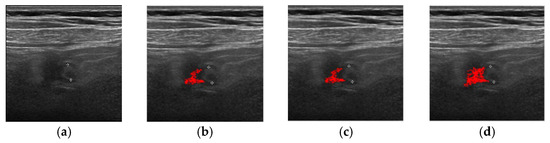

| Method | Successful Images/Total Images |

|---|---|

| FCM | 83/100 |

| ORFCM | 88/100 |

| DFCM | 91/100 |

| DORFCM | 98/100 |